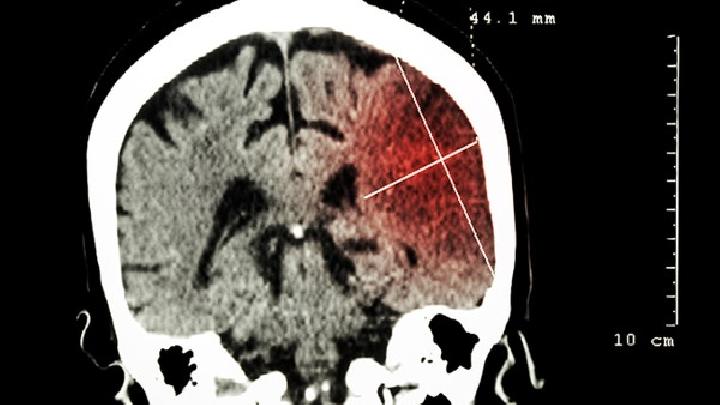

脑萎缩症状都有哪些?专家指出,老年性痴呆脑萎缩症状以隐袭起病、持续进行性的智能衰退为特征,记忆障碍通常显本病的首发症状,而后出现视空间技能损害、思维及判断能力障碍、语言障碍、计算障碍等大脑高级功能障碍以及行为异常等症状。

大脑萎缩的症状表现主要有记忆力减退、认知功能障碍、运动协调障碍、情绪性格改变。症状发展通常从早期轻微认知下降逐渐...